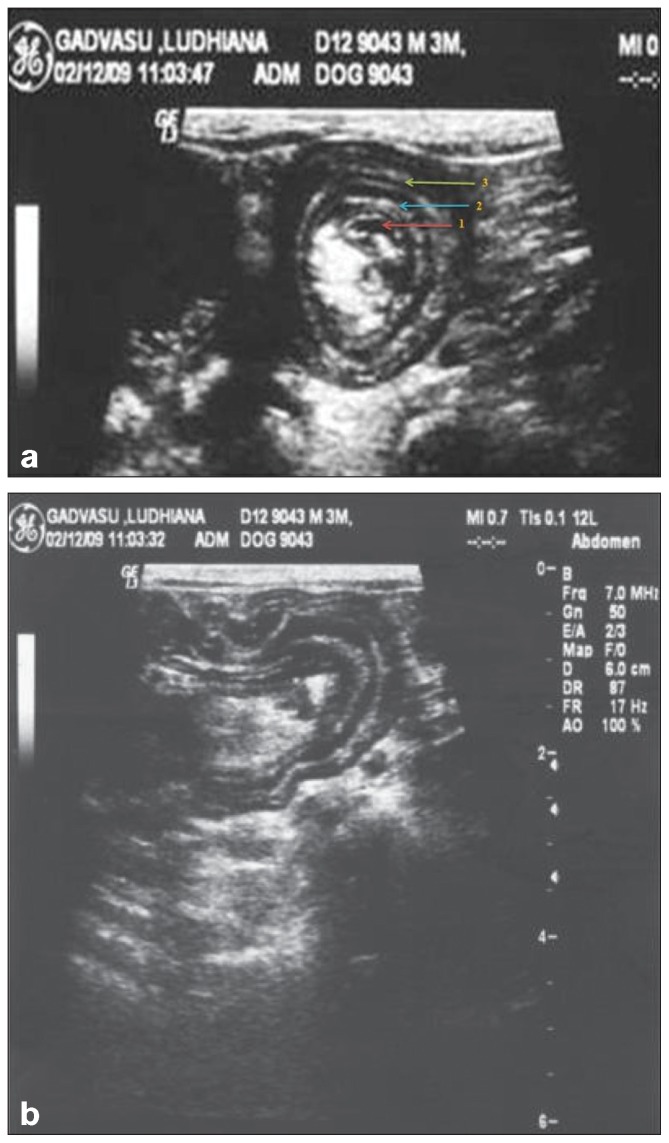

Figure 3. Longitudinal ultrasound view of intussusception showing multiple parallel hyperechoic and hypoechoic layers within the lumen of the intussuscipiens.

| Multiple Parallel Lines (Longitudinal) | Alternating hyperechoic and hypoechoic linear streaks; "sandwich sign" |

| Pseudokidney Sign | Seen when intussusception is curved and mesentery visible on one side; resembles kidney shape |

| Hyperechoic Crescent | Invaginated mesentery appears as hyperechoic semilunar structure; may see congested vessels within |

| Associated Findings | Proximal bowel dilation, fluid accumulation, hyperperistalsis (acute) or absence of peristalsis (chronic), peritoneal effusion |

Board Tip - Memory Aid: "TARGET your diagnosis with ultrasound!" The TARGET SIGN is pathognomonic for intussusception. Think of it like looking at a dartboard (target) from above - you see concentric rings. On longitudinal view, you see "stacked pancakes" or parallel lines.

Figure 3 - Lateral radiograph showing gas-distended intestinal loops (Case 2, double intussusception): Aprea F et al. (2012). Can Vet J. Figure 1. PMC3398523. URL: https://pmc.ncbi.nlm.nih.gov/articles/PMC3398523/ - Open Access.